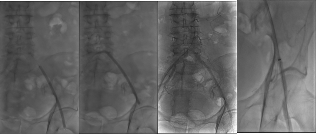

影像1:术前测量及三维影像

术前详解

(1)髂总动脉开口处病变,需要支架能够精准定位,既不能覆盖腹主动脉分叉型处遮挡对侧血流,又不能向髂总动脉内移牺牲有效锚定区。

(2)病变全长约115mm,预计覆盖血管全长约135mm。LCA=7.4mm,LEIA=5.7mm,要实现6mm到8mm的直径渐变。

(3)LIIA起始部重度狭窄,RIIA完好,双侧股深动脉,股浅动脉均正常。